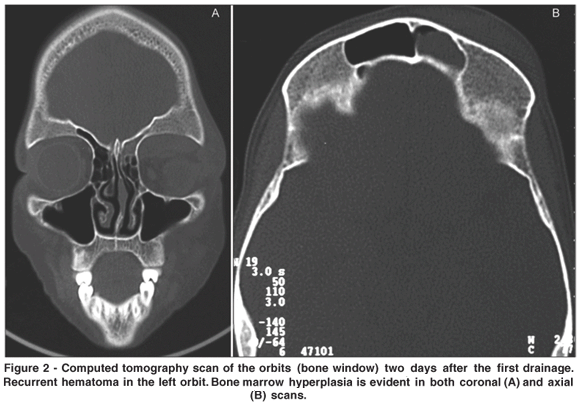

An 11-year-old girl with SCD presented to the emergency room with visual loss after being hit in the left frontal region by a mud pie. On examination, the left eye was grossly proptotic with inferolateral dystopia, important eyelid swelling and afferent pupillary defect (Figure 1A). Visual acuity was 20/20 in the right eye and counting fingers in the left eye. Slit lamp examination was normal in both eyes. Computed tomography of the orbits showed a superomedial subperiosteal hematoma (Figure 1B). The patient underwent an urgent canthotomy, cantholysis and drainage of the hematoma through a lid crease approach. On the first postoperative day proptosis was reduced, the pupillary reflexes were normal and the visual acuity improved to 20/40. However, as the globe displacement persisted the patient was transferred to the Oculoplastic Clinic of the School of Medicine of Ribeirão Preto. A second CT scan of the orbits showed an important subperiosteal hemorrhage. Hypertrophy of the diploic spaces of the calvarium bones was evident, especially in the left frontal bone (Figure 2). New surgical exploration was performed through the same eyelid crease approach and the periosteum was widely opened at the superior orbital rim. Exposure allowed the visualization of multiple bone erosions on the orbit roof with persistent bleeding (Figure 3).

Orbital compression syndrome has already been described in patients with SCD 3, including a first report in the Brazilian literature(4). However, the usual presentation is an acute event dominated by inflammatory signs resulting from bone infarction. In the present case, after a minor trauma the patient presented with an important subperiosteal hematoma without signs of inflammation. Surgical exploration revealed that the frontal bone was abnormally thickened with multiple holes on the orbital rim and along the roof (Figure 3). We believe that this abnormality was caused by the bone marrow hyperplasia found at several skeletal sites including the skull. In normal adults bone marrow is found mainly in the axial skeleton. However, in children with SCD the marrow is expanded into all of the bones. In the skull the typical finding is as an expansion of the diploic space with thinning of both outer and inner tables. This process is an attempt of the organism to increase erythrogenesis and thus represents a response to chronic anemia. Bone marrow hyperplasia, which is usually more severe in sickle cell thalassemia, can be demonstrated by a variety of imaging techniques including scans with radionuclides, magnetic resonance imaging, computed tomography, and plain films(5). In our case bone marrow hyperplasia of the roof was the underlying condition that caused bleeding after the minor frontal trauma. This event is similar to hemarthrosis, an uncommon complication occurring in sickle cell anemia(5). Orbital surgeons should be aware of the fact that orbital bleeding without signs of infarction is due to an intrinsic bone weakening that must be specifically addressed.